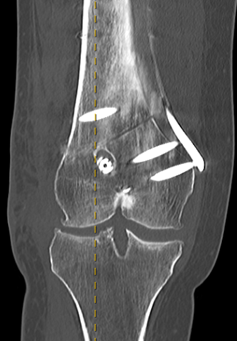

Preoperative Planning

AP full length standing xrays

Line from centre of talus to desired mechanical axis

Line from centre of femoral head to desired mechanical axis

a) is the desired angle of correction

Valgus OA Preop PlanningDFVO preopDistal Femoral Osteotomy Postop View